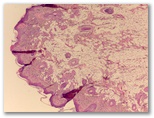

¿fibroma blando?

Diagnostico